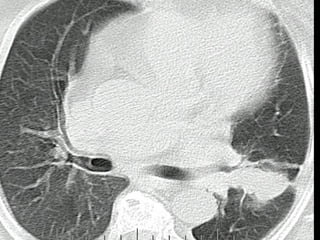

Nódulo pulmonar Indeterminado

Chest radiograph of a patient with bilateral pulmonary metastases from endometrial

cancer. The mass in the right upper lobe is well circumscribed and has the radiographic

appearance typical of a metastasis.